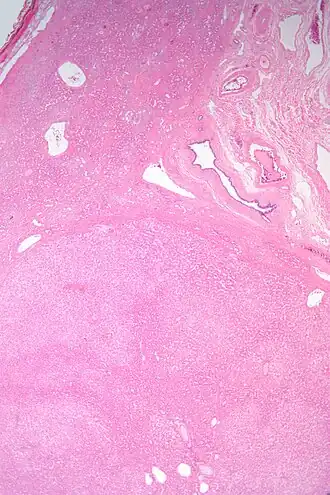

Coupe histologique d'un adénome hépatocellulaire. Coloration H&E